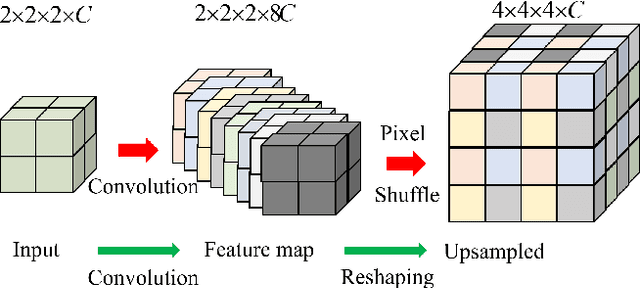

Abstract:Complicated image registration is a key issue in medical image analysis, and deep learning-based methods have achieved better results than traditional methods. The methods include ConvNet-based and Transformer-based methods. Although ConvNets can effectively utilize local information to reduce redundancy via small neighborhood convolution, the limited receptive field results in the inability to capture global dependencies. Transformers can establish long-distance dependencies via a self-attention mechanism; however, the intense calculation of the relationships among all tokens leads to high redundancy. We propose a novel unsupervised image registration method named the unified Transformer and superresolution (UTSRMorph) network, which can enhance feature representation learning in the encoder and generate detailed displacement fields in the decoder to overcome these problems. We first propose a fusion attention block to integrate the advantages of ConvNets and Transformers, which inserts a ConvNet-based channel attention module into a multihead self-attention module. The overlapping attention block, a novel cross-attention method, uses overlapping windows to obtain abundant correlations with match information of a pair of images. Then, the blocks are flexibly stacked into a new powerful encoder. The decoder generation process of a high-resolution deformation displacement field from low-resolution features is considered as a superresolution process. Specifically, the superresolution module was employed to replace interpolation upsampling, which can overcome feature degradation. UTSRMorph was compared to state-of-the-art registration methods in the 3D brain MR (OASIS, IXI) and MR-CT datasets. The qualitative and quantitative results indicate that UTSRMorph achieves relatively better performance. The code and datasets are publicly available at https://github.com/Runshi-Zhang/UTSRMorph.